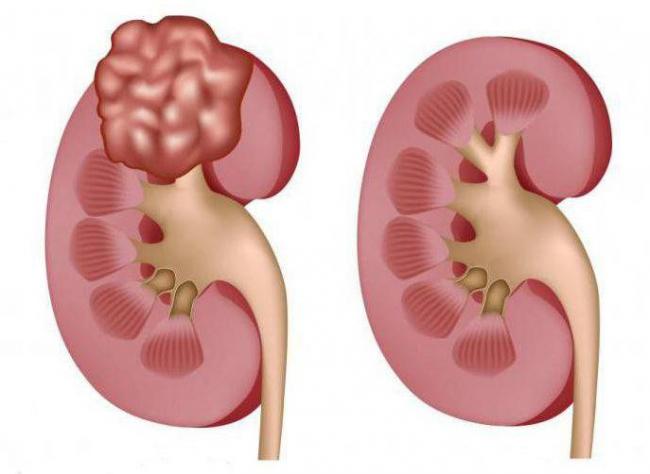

Как правило, в связи с патологическими изменениями в почках возможно появление доброкачественных или злокачественных опухолей. К отличительным особенностям первых можно отнести медленный рост, благоприятный прогноз (при своевременном выявлении) и отсутствие прорастаний в рядом лежащие клетки. Стоит отметить, что при почечно-клеточном раке (ПКР) образование отличается высокой предрасположенностью к появлению метастаз.

Опухолью почки называется очаговое образование, связанное с патологическим разрастанием почечной паренхимы, в состав которой входят патологически изменившиеся клетки. От характера роста опухоли классифицируются на злокачественные и доброкачественные.

Доброкачественное образование менее агрессивно. Порой оно настолько незначительно, что даже не вызывает дискомфорта и не нарушает привычную жизнедеятельность органа. Опухоль характеризуется медленным ростом, при ее развитии не нарушается структура ткани и не образуются метастазы.

Доброкачественные новообразования на ранней стадии не нарушают функции органа. Опухоль растет медленно, структура ткани не разрушается, метастазы не образуются.

Однако, при росте объма образование оказывает негативное действие на мочевыводящую систему, повреждает сосуды, вызывает кровотечение. Имеется риск преобразования доброкачественной опухоли в онкологическую.